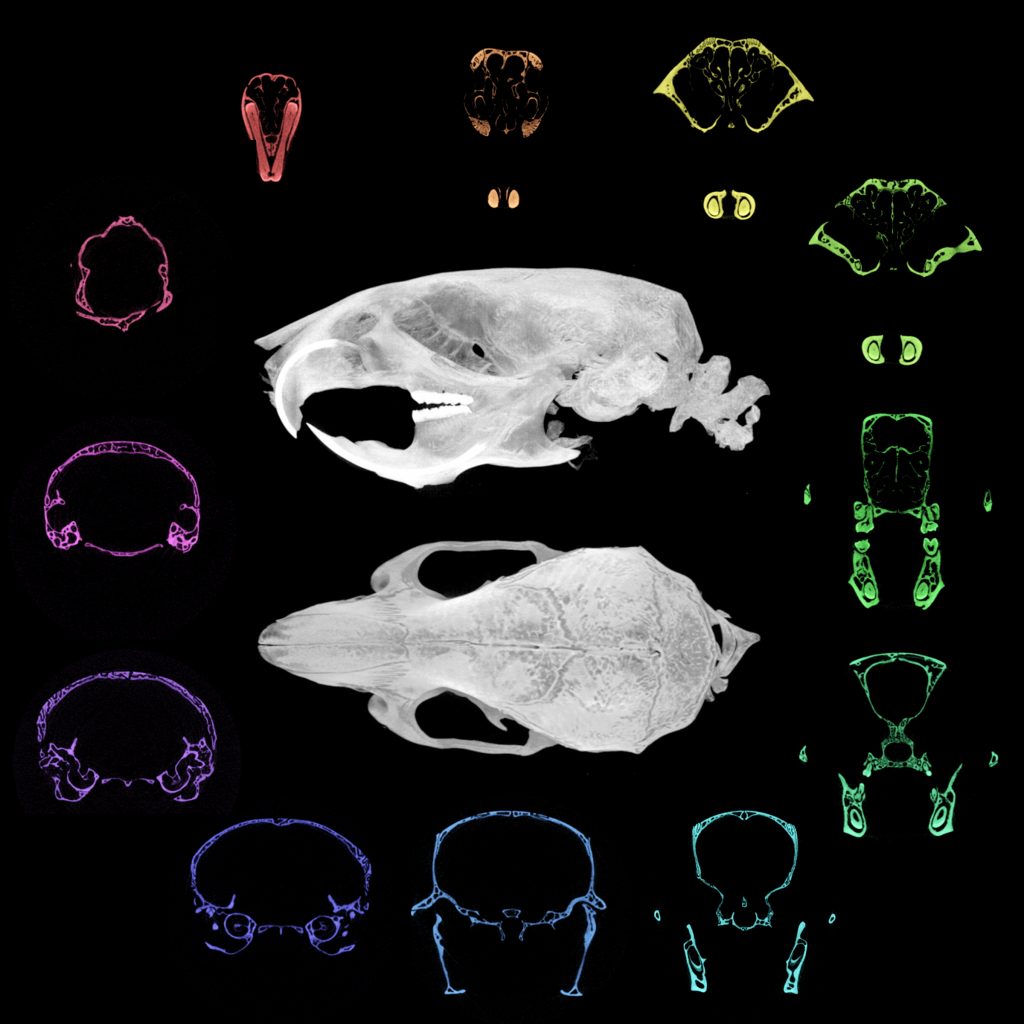

Micro-computed tomography of the adult mouse craniofacial skeleton, highlighting different bone structures (coloured). Credit: Dr Tiffany Chern (previous graduate student at the Poché lab)

Their recent studies on cblX mice revealed not only the expected nervous system problems but also new craniofacial defects – changes in the shape of the skull and face. This discovery broadens understanding of how the disorders impact different tissues and could guide the development of treatments that address both metabolic and structural problems.